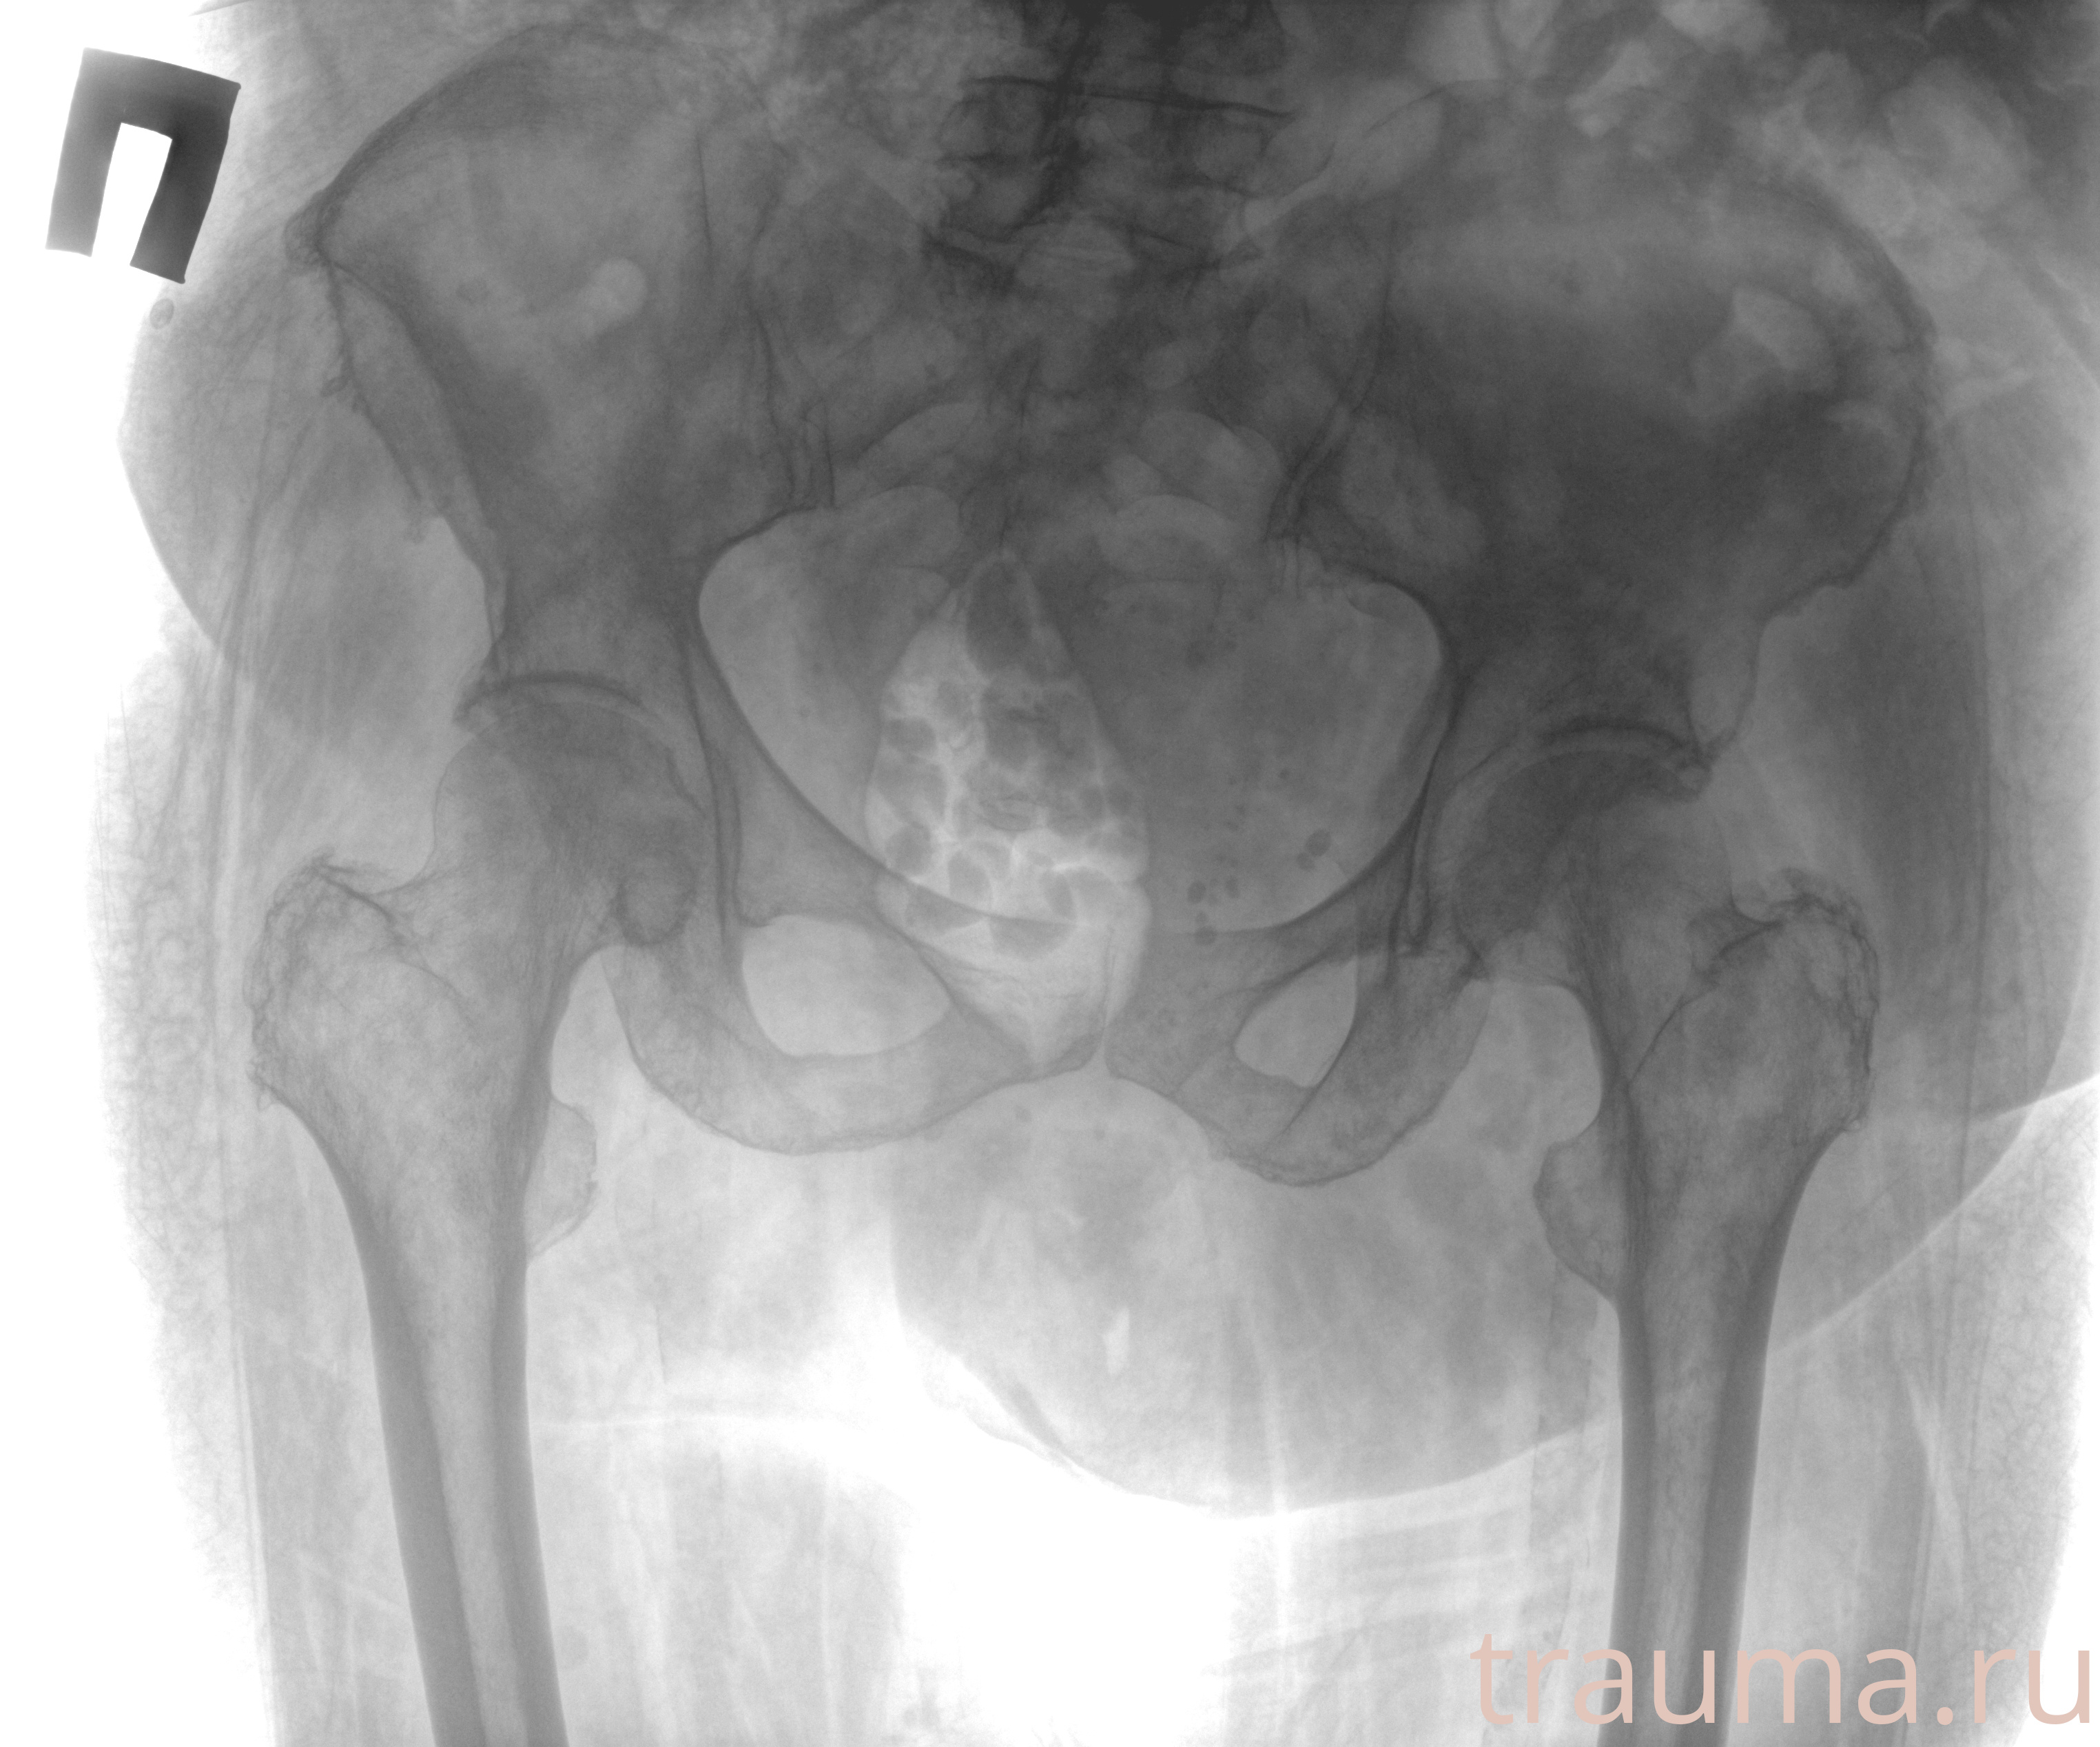

Рентгенограммы

Рентген на дому: по вашему адресу приезжает врач-рентгенолог, травматолог-ортопед с мобильным рентгеновским аппаратом, проводит диагностику травмы или заболевания, делает необходимые рентгенограммы, дает рекомендации по дальнейшему лечению. Получить качественные снимки в домашних условиях возможно благодаря уникальной методике, разработанной МосРентген Центром для института  Склифосовского